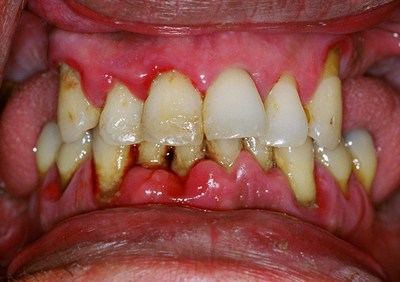

A periodontite agressiva juvenil é uma doença gengival séria que afeta jovens. Ela causa destruição rápida do osso e dos tecidos que sustentam os dentes. O diagnóstico precoce é crucial para evitar a perda dentária.

A regeneração tecidual entra em cena depois que a inflamação está sob controle. O objetivo é recuperar os tecidos que foram danificados pela doença. Isso pode envolver procedimentos como raspagem e alisamento radicular para limpar as bolsas periodontais. Em casos mais avançados, a gente pode pensar em enxertos ósseos ou de gengiva, tudo para ajudar o corpo a se reconstruir.

Vamos falar sério agora sobre periodontite agressiva juvenil. Se você ou alguém que você conhece está lidando com isso, sabe que é um assunto delicado. Basicamente, quando a doença periodontal avança e a inflamação já causou perdas ósseas significativas, a cirurgia pode ser o caminho. É aquela situação em que a limpeza profunda que fazemos não consegue mais alcançar as bactérias mais problemáticas.

Eu já vi casos onde a gengiva se retrai muito, deixando a raiz do dente exposta. Isso não é só questão estética, viu? Aumenta a sensibilidade e o risco de cáries nessa área. A cirurgia periodontal entra para tentar recuperar o suporte dos dentes, removendo as bolsas periodontais e, em alguns casos, até regenerando o osso perdido. É um procedimento para quando outras abordagens não foram suficientes, entende?

O objetivo principal da cirurgia é tornar a área mais fácil de limpar, removendo as bactérias que se escondem nas bolsas profundas. Isso ajuda a parar a progressão da doença e a salvar os dentes. É um passo importante para quem busca um tratamento mais completo contra a periodontite agressiva juvenil, pensando na saúde bucal a longo prazo.